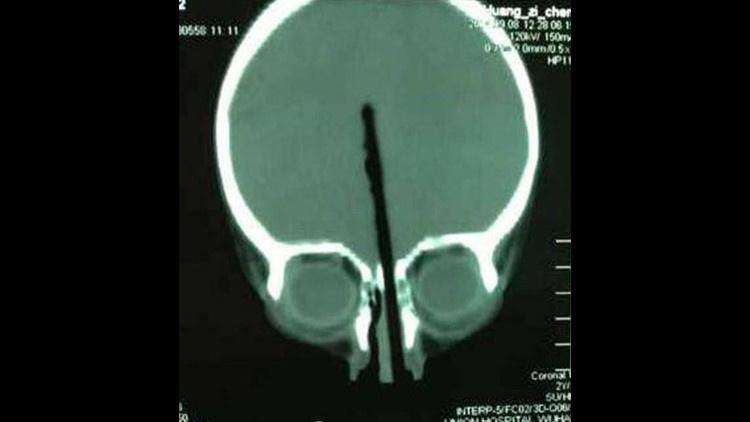

نجح أطباء صينيون في إخراج عصاة من رأس طفل كان قد غرزها في أنفه لتخترق نحو 8 سنتميرات من دماغه.

ويقول والد الطفل هوانغ زيشنغ البالغ من العمر عامين أنه لا يعرف كيف أو لماذا غرز طفله عصاة الطعام في أنفه مخترقة ما يقرب من 8 سنتيمترات داخل دماغه.

وقد نُقل الطفل هوانغ إثر ذلك إلى مستشفى في مقاطعة هوبي الصينية، حيث أجرى الأطباء جراحة عاجلة استغرقت نحو أربع ساعات كاملة، ونجحوا في إخراج العصاة من رأس هوانغ.

ويقول الأطباء إن الطفل خرج من العملية سليما، وأن العصاة لم تطل أيا من الأعصاب أو الشرايين داخل دماغه، وينتظر خلال شهور قليلة أن يتعافى بصورة كاملة.